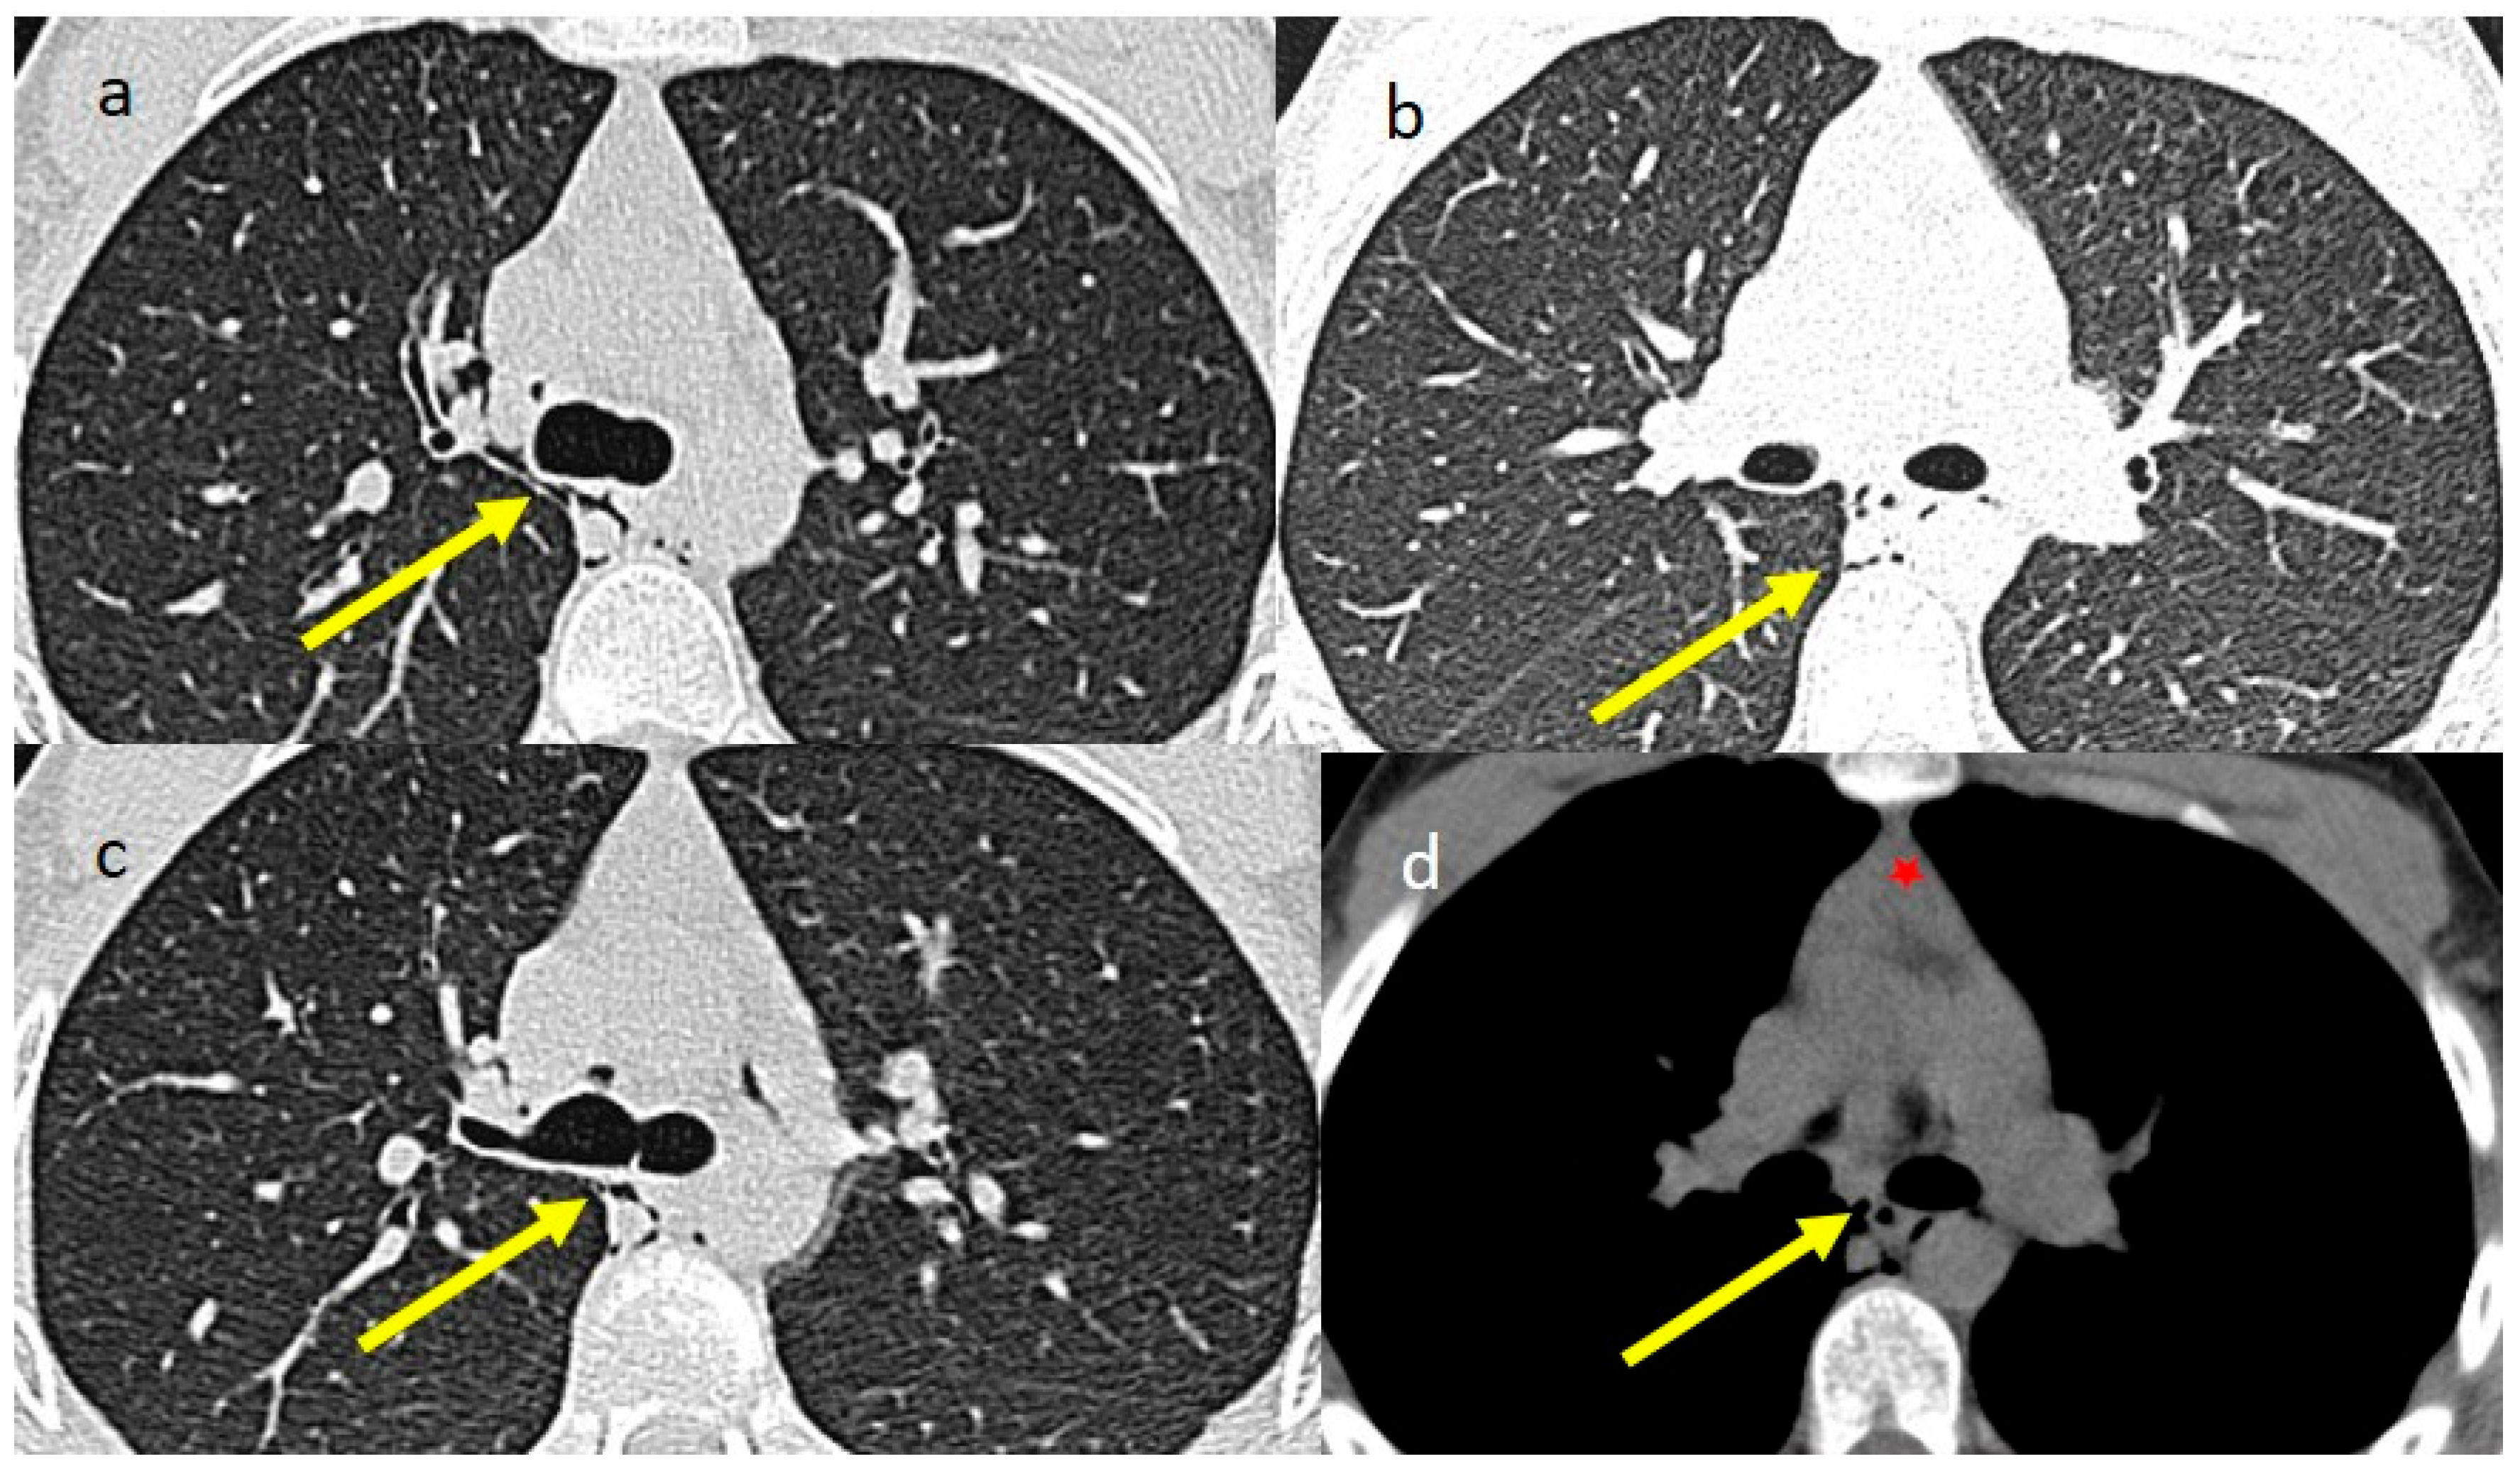

2. Case Presentations

3.2. Thymic Hyperplasia in COVID-19 Infection and Vaccination and the Role of Multimodality Imaging